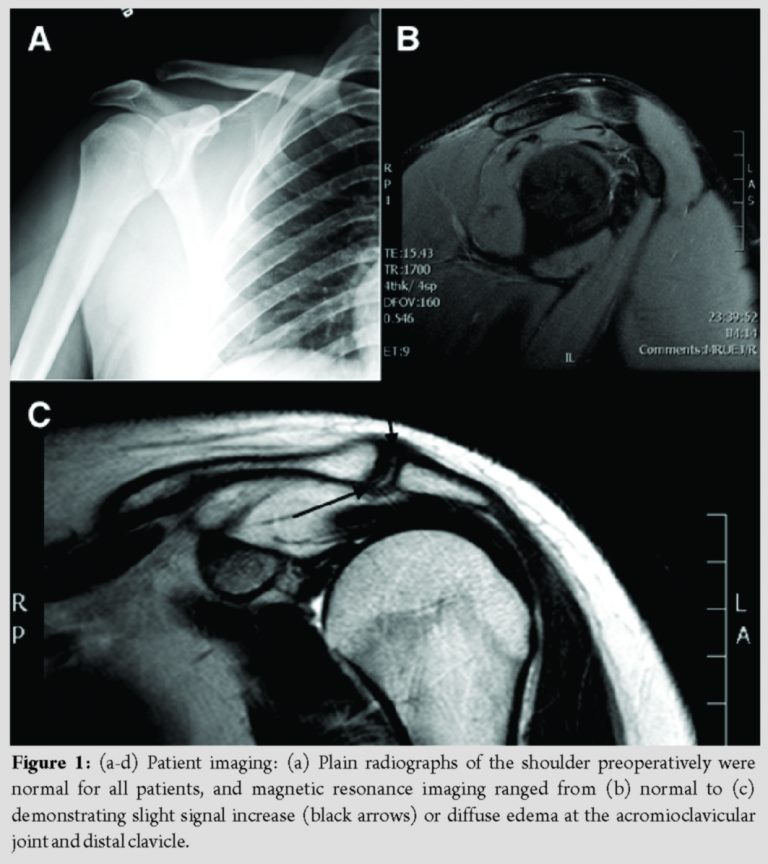

Imaging

Radiographs were unremarkable and indicated no evidence of arthritis, fracture, or dislocation. The AC joint was normal or at the upper limits of normal (Fig. 1a). Magnetic resonance imaging (MRI) ranged from completely normal (Fig. 1b) to displaying significant changes about the AC joint, including hypertrophied tissue on the undersurface of the AC joint, distal clavicle marrow edema, and increased signal density between the thinned fibrocartilage disk and the chondral surface of the distal acromion (Fig. 1c). Other findings included one patient demonstrating a small amount of signal in the supraspinatus, suggesting a 2–3 mm partial thickness rotator cuff tear. Another showed mild increase in signal in the supraspinatus tendon with no evidence of a tear of the musculotendinous junction. This same patient had some slight signal increase in the anterior aspect of the superior labrum, but it was thought that this was more representative of the sublabral cleft representing a small tear without displacement. One patient with imaging data available had an incidental cyst beneath the posterior superolateral humeral head margin. All other available findings were otherwise normal.